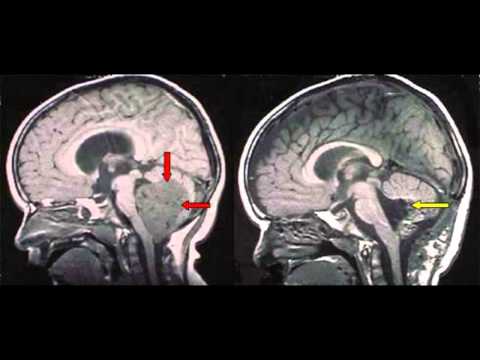

Signs Of Brain Cancer In Infants - Brain Cancer Pictures : Brain tumors can occur at any age.. Possible signs and symptoms of cancer in children many cancers in children are found early, either by a child's doctor or by parents or relatives. The most common brain tumor in children is medulloblastoma. Brain tumors and other nervous system tumors make up about 27 percent of childhood cancers. Pediatric brain tumors include medulloblastoma, glioma, embryonal tumor, germ cell brain tumor, spinal cord tumor, craniopharyngioma and pineoblastoma. Many children will experience visual abnormalities such as abnormal eye movements and changes to their vision.

Brain tumors can occur at any age. But cancers in children can be hard to recognize right away because early symptoms are often like those caused by much more common illnesses or injuries. Brain tumour symptoms in children. Stage 2 is marked by the slow growth of cancer cells, which may spread into neighboring cells and develop into a higher stage of tumor that is more aggressive; Pediatric brain tumors include medulloblastoma, glioma, embryonal tumor, germ cell brain tumor, spinal cord tumor, craniopharyngioma and pineoblastoma.

Brain tumors can be invasive (destroying nearby tissue or travelling to other spots in the body) or noninvasive (moving nearby tissue aside to grow larger). Tumors at the base of the brain often cause headaches, vomiting, and behavioral changes because they block the normal passage of cerebrospinal fluids, causing the pressure within the head to rise. Problems speaking clearly, swallowing, or walking headaches along with vomiting, especially in the morning These will depend on the size of the tumour, where it is and how it affects that part of the brain. While brain tumours are rare, it is important to be aware of brain tumour symptoms, so you can go to your doctor if you are concerned. Most commonly, children present with symptoms described below. Stage 2 is marked by the slow growth of cancer cells, which may spread into neighboring cells and develop into a higher stage of tumor that is more aggressive; You can detect brain tumor in your child with the help of some signs and symptoms. What are the signs of cancer in babies? Other children may be too young to communicate them. Brain tumors in children make up about 15% of pediatric cancers. Pdf | the presenting symptoms and signs of intracranial tumors diagnosed before the age of 2 years in 21 children treated at the university hospital of. A tumour in the brain can come from the brain itself (primary), or from another part of the body (secondary).

Brain tumors can be invasive (destroying nearby tissue or travelling to other spots in the body) or noninvasive (moving nearby tissue aside to grow larger). When a child develops a brain tumor, early diagnosis is essential. Brain tumor in children pediatric brain tumors are masses of abnormal growth that occur in the brain or the in tissues and structures that are near to it. Tumors at the base of the brain often cause headaches, vomiting, and behavioral changes because they block the normal passage of cerebrospinal fluids, causing the pressure within the head to rise. Signs or symptoms of brain tumors will depend on things such as the age of the child and the location of the tumor in the brain.

| find, read and cite all the research. Pdf | the presenting symptoms and signs of intracranial tumors diagnosed before the age of 2 years in 21 children treated at the university hospital of. But cancers in children can be hard to recognize right away because early symptoms are often like those caused by much more common illnesses or injuries. Problems speaking clearly, swallowing, or walking headaches along with vomiting, especially in the morning There are many other that affect children, including astrocytomas, gliomas, ependymomas, germinomas and more. In children, tumors usually start in a part of the brain that controls movement and coordination. Most brain tumors in children start in the lower parts of the brain, such as the cerebellum or brain stem. Headaches, which may become more frequent and more severe feeling of increased pressure in the head unexplained nausea or vomiting Signs of brain tumors in infants. This increase in intracranial pressure can lead to general health concerns such as: Keeping those caveats in mind, what are the signs and symptoms of brain tumors in children? An increase in head size in infants; They can be cancerous or noncancerous.

The symptoms of a pediatric brain tumor vary according to the size, type and location of the tumor. Increased intracranial pressure (icp) vomiting (usually occurs in the morning without nausea) Babies with cancer can have many different symptoms, depending on what type of cancer it is. | find, read and cite all the research. A tumour in the brain can come from the brain itself (primary), or from another part of the body (secondary). They may also occur when the brain swells or there is fluid buildup in the skull. Increased intracranial pressure is caused by extra tissue in the brain as well as blockage of the cerebrospinal fluid flow pathways. Headache many children with a brain tumor experience headaches before their diagnosis. Headaches, which may become more frequent and more severe feeling of increased pressure in the head unexplained nausea or vomiting The most common symptoms include: Brain cancer is divided into four progressive and overlapping stages. The following article provides information about the various symptoms of this condition. Most of these are not caused by a brain tumour.